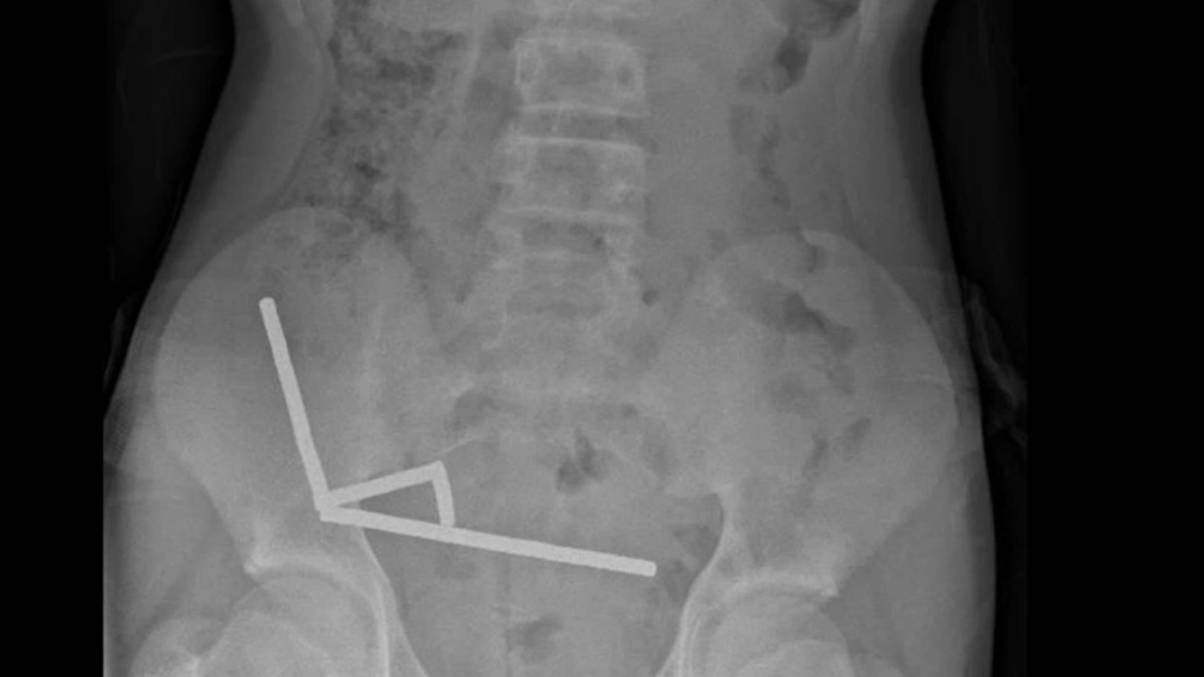

X-rays then revealed that the magnets – which have been banned in New Zealand since 2013 – had been linked in ‘4 linear chains’ inside his intestines.

The medical doctors behind the report, Binura Lekamalage, Lucinda Duncan-Have been and Nicola Davis, wrote: “These gave the impression to be in separate components of bowel adhered collectively because of magnetic forces.”

“Intraoperative findings had been of a number of chains of magnets at completely different segments of small bowel and caecum,” it continued.

“These had been adhered at a number of factors in the correct decrease quadrant inflicting strain necrosis.”